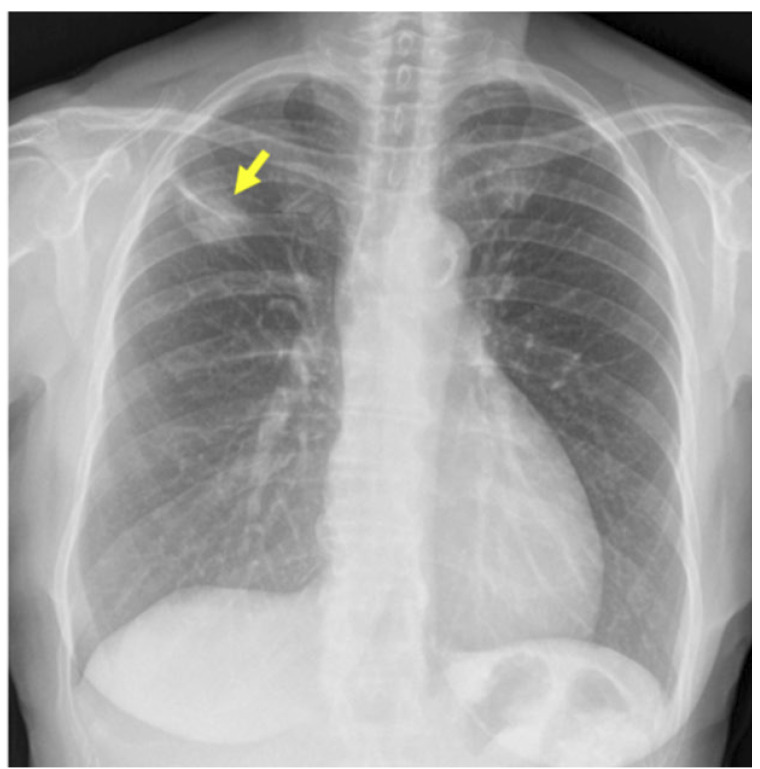

Multiple primary lung cancer can be synchronous or metachronous based on the timing of lesion onset. Despite the existing classification criteria for lung cancer with multiple lung involvement, it is sometimes challenging to distinguish between lung cancer with multiple lung involvement and intrapulmonary metastases. Moreover, differentiating synchronous multiple primary lung cancer from multifocal ground-glass/lepidic-pattern lung cancer is crucial. While histologic evaluation can aid in diagnosis, molecular analyses are often necessary. We present the case of a female patient diagnosed with triple synchronous primary lung adenocarcinomas. Although the lesions shared the same histological subtype, they exhibited distinct histological patterns and molecular profiles. In cases of lung cancer with multiple lung involvement, it is essential to perform a detailed pathological study for an accurate diagnosis and appropriate therapeutic interventions.